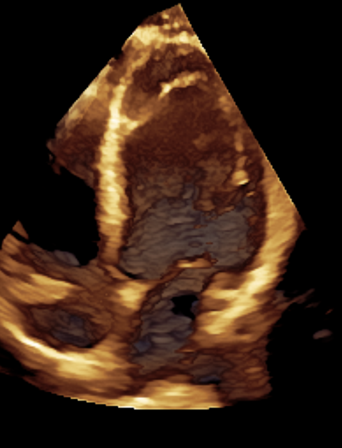

3D echocardiografie geeft een veel gedetailleerder en completer beeld van het hart dan traditionele 2D echocardiografie. In plaats van alleen beelden van het hart in zijaanzicht of bovenaanzicht te tonen, kunnen we nu de interne structuren van het hart vanuit verschillende hoeken bekijken en zelfs 'virtueel' door het hart heen kijken.

Als laatst wordt 3D echocardiografie al langere tijd toegepast bij de analyse van de oorzaak van hartklepafwijkingen. Met name bij slokdarmechocardiografie, maar ook bij transthoracale echocardiografie (als de beeldkwaliteit het toelaat) kunnen 3D beelden van de hartklep worden gemaakt. Dit helpt de cardioloog en de hartchirurg om beter te begrijpen waarom een hartklep lekt en hoe dit gerepareerd zou kunnen worden. Daarnaast worden er steeds met klepingrepen via de bloedvaten in de lies uitgevoerd. Deze ingrepen worden begeleid middels slokdarmechocardiografie en hierbij kunnen we inmiddels niet meer zonder de 3D beeldvorming.